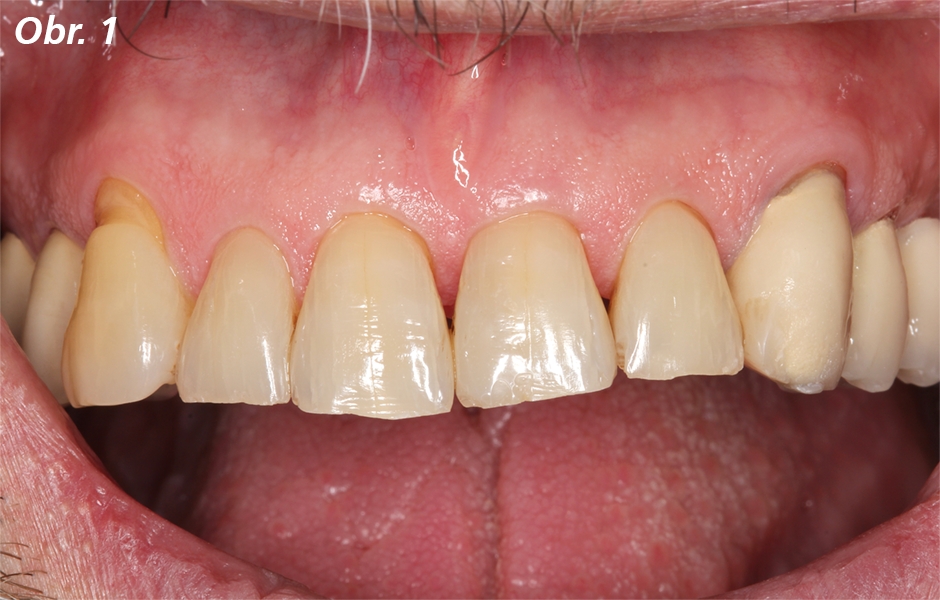

Pacient s metalokeramickými korunkami se dostavil s meziálně- incizálním odlomením keramiky na zubu 23 (obr. 1, 2). Korunky byly nasazeny předchozím zubním lékařem. Pacient chtěl precizně rekonstruovat tvar korunek, použité materiály nebyly známy. Pacient měl problém hlavně s estetikou a hrubostí povrchu odlomené keramiky. Klinické vyšetření odhalilo věku odpovídající zuby s protetickými a přímými konzervativními rekonstrukcemi. Byly zjištěny všeobecně mírné gingivální recesy, výraznější v oblasti špičáků. Orální hygiena byla dobrá, okraj korunky zubu 23 byl obnažen, ale nevykazoval žádné klinické abnormality (obr. 2). Ani korunka ani okraj korunky v současném stavu nebyly důvodem pro výměnu celé korunky. Během konzultace s pacientem proto bylo rozhodnuto ve prospěch přímé, intraorální opravy pomocí nanohybridního kompozita Charisma Diamond. Odlomení keramiky na zubu 23 patřilo mezi tzv. jednoduchá odlomení, což znamená, že povrch lomu je celý v keramice, bez obnažení kovové konstrukce. Po vyleštění opravovaného zubu byl nasazen kofferdam a okraje poškozeného keramického povrchu byly pomocí jemného diamantu rozšířeny o zhruba 1 mm nad okraje lomu. Poté byl celý opravovaný povrch zdrsněn karbidkřemičitým kaménkem, důkladně opláchnut vodní sprchou a osušen. Nyní bylo možné opracovaný keramický povrch snadno odlišit od ostatních částí (obr. 3). Alternativně je také možné povrch intraorálně opískovat oxidem hlinitým, přičemž je třeba chránit měkké tkáně. Předchozí rizikové intraorální ošetření povrchu silikátové keramiky kyselinou fluorovodíkovou je vynecháno. Na čistý a suchý povrch preparovaného keramického povrchu se nanese tenká vrstva primeru GLUMA Ceramic Primer (obr. 4).

Počáteční situace vykazuje metalokeramickou náhradu s meziálním kohezním odlomením keramiky na zubu 23